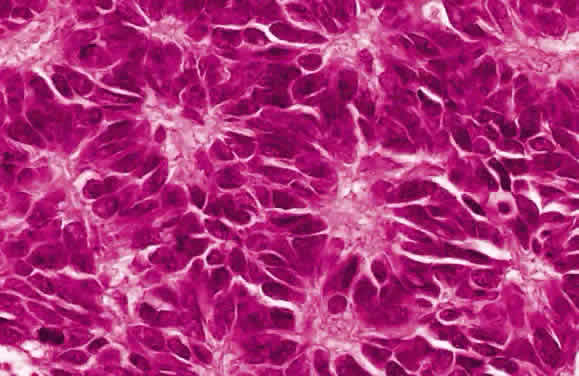

HISTOLOGY AND ULTRASTRUCTURE